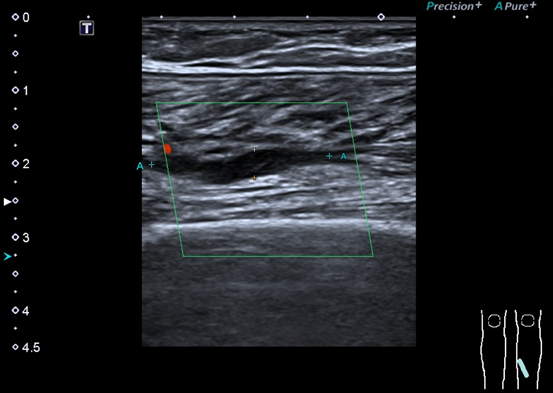

血管彩超是诊断和随访肌间静脉血栓最常用的影像学手段(上图所示为比目鱼肌静脉丛血栓)

血管彩超是诊断和随访肌间静脉血栓最常用的影像学手段。